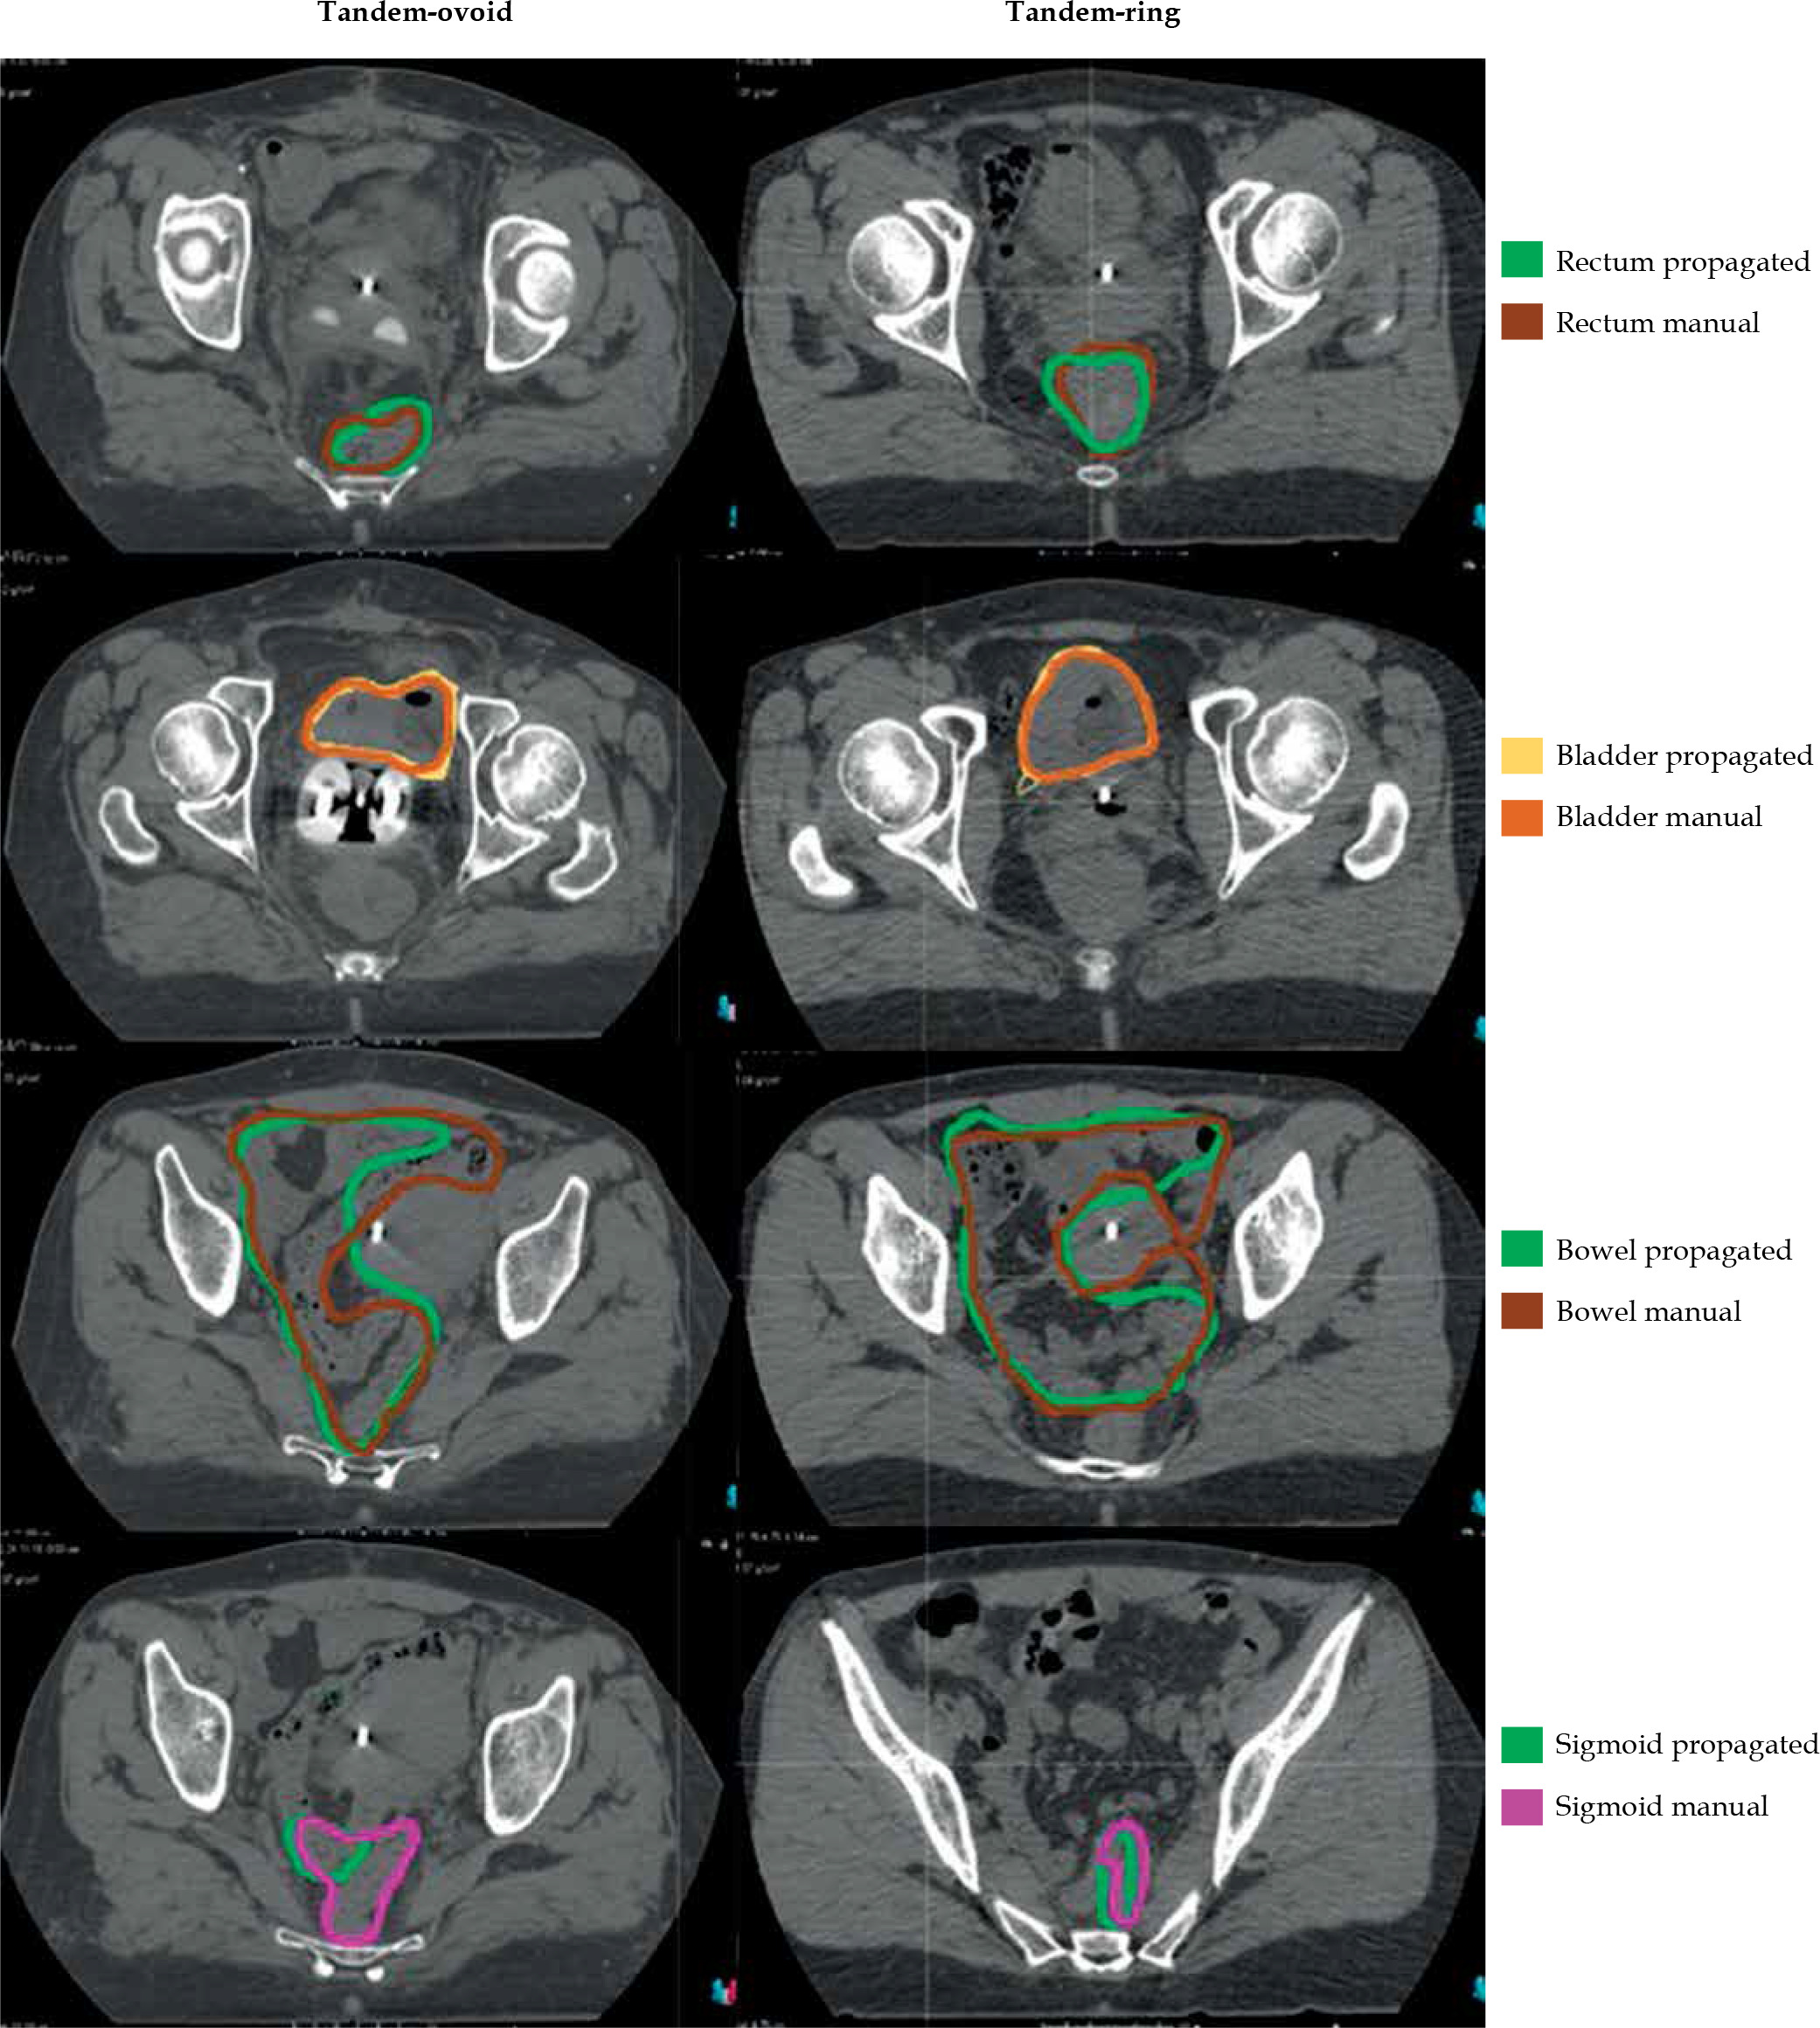

Figure 1 displays CT images of two patients who underwent T-R and T-O insertion each. In both insertions, the overlapping of the applicators was provided with DIR. Figure 1 also shows HR-CTV and IR-CTV volumes, which were delineated manually or automatically. Comparisons of manual and automatically-propagated contours of OARs for these patients are provided in Figure 2.

Fig. 2

Organs at risk volumes defined manually or automatically before and after deformable image registration

Table 3 shows DSC scores of the automatically-propagated and manual contours for both T-O and T-R applications. These results indicate that the contour similarities between the manual and automatic segmentation are weakest for the sigmoid and small bowel for both insertions. Furthermore, the automatic segmentation of the rectum for T-R insertion is much better than that for T-O insertion.

DIR is a great challenge for the rectum, since it may vary in shape and content in each application [30]. To reduce this variation, all our patients received a rectal enema prior to each BT fraction, and a CT scan was performed to verify the emptiness and distension of the rectum. The DSC score was quite satisfying for the rectum when T-R was used. However, when T-O was used, the mean DSC score was only 0.58, which was significantly lower, even with the same rectal protocol. We believe that this was mainly due to the rectal retractor associated with T-R applicator. Since there was no retractor in the T-O applicator in our study, the differences in the amount of rectal packing may have caused this low DSC score. The DSC score for the rectum showed that DIR-based automatic contouring was useless for the T-O insertion.

The main mismatch between the manual contouring and DIR in our study was for the sigmoid and small bowel. Since there were no fixations for the small bowel and sigmoid, they were free to move more independently from the cervix and applicator than were the bladder and rectum. Similar results were reported by Nesvacil et al. [31] with lowest volumetric uncertainties for the bladder and the rectum, and highest for the sigmoid.